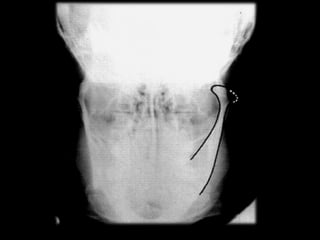

Ankylosis treated with total joint prosthesis

Panoramic view shows prosthesis (arrow), consisting of artificial fossa (fixed with six

titanium screws in temporal bone), and artificial condylar process (fixed with seven titanium

screws to mandibular ramus

Ankylosis treated withtotal joint prosthesis Panoramic view shows prosthesis (arrow), consisting of artificial fossa (fixed with six titanium screws in temporal bone), and artificial condylar process (fixed with seven titanium screws to mandibular ramus